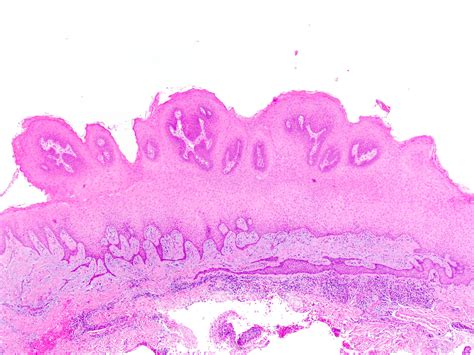

An Oral Squamous Papilloma is a benign, exophytic growth resulting from an infection caused by the Human Papillomavirus (HPV), most commonly types 6 and 11. Unlike malignant tumors, these papillomas are non-cancerous and do not have the potential to spread to other parts of the body (metastasize). They typically appear as solitary, painless, white-to-pink lesions with a roughened, pebbly surface.

Identifying an Oral Squamous Papilloma often involves observing its distinct morphology. Clinicians look for specific visual cues that differentiate this lesion from other oral pathologies like focal epithelial hyperplasia or squamous cell carcinoma. Because they are exophytic, they grow outward from the surface, often resembling a small cluster of grapes or a delicate cauliflower head.

Texture Rough, papillary, or cauliflower-like